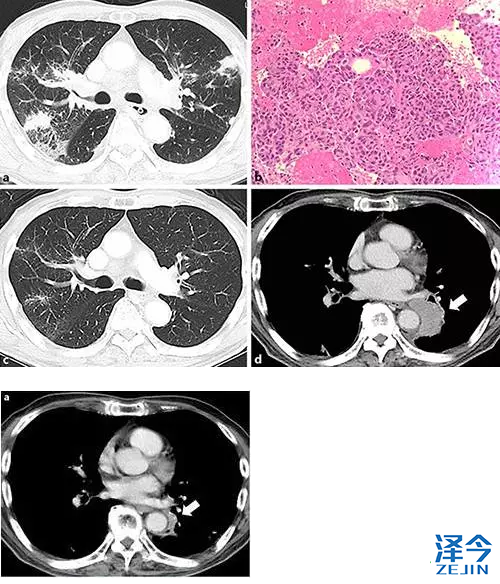

一名有59年吸烟史的76岁男子,因嘶哑,吞咽困难及体重减轻就诊。 耳鼻喉科检查发现左声带瘫痪。 使用增强(CT)进行检查,其显示双侧肺门区域,纵隔和颈部的肺和淋巴结病中的多个结节。 经进一步检查,他被诊断患有肺腺癌(cT1aN3M1a,IV期)(图1a,b)。 基因检测显示ALK融合基因阳性。

nivolumab治疗后肺癌CT检查及胃癌内镜检查。 a在给予nivolumab 5周后,肺部病变显示明显改善(箭头)。